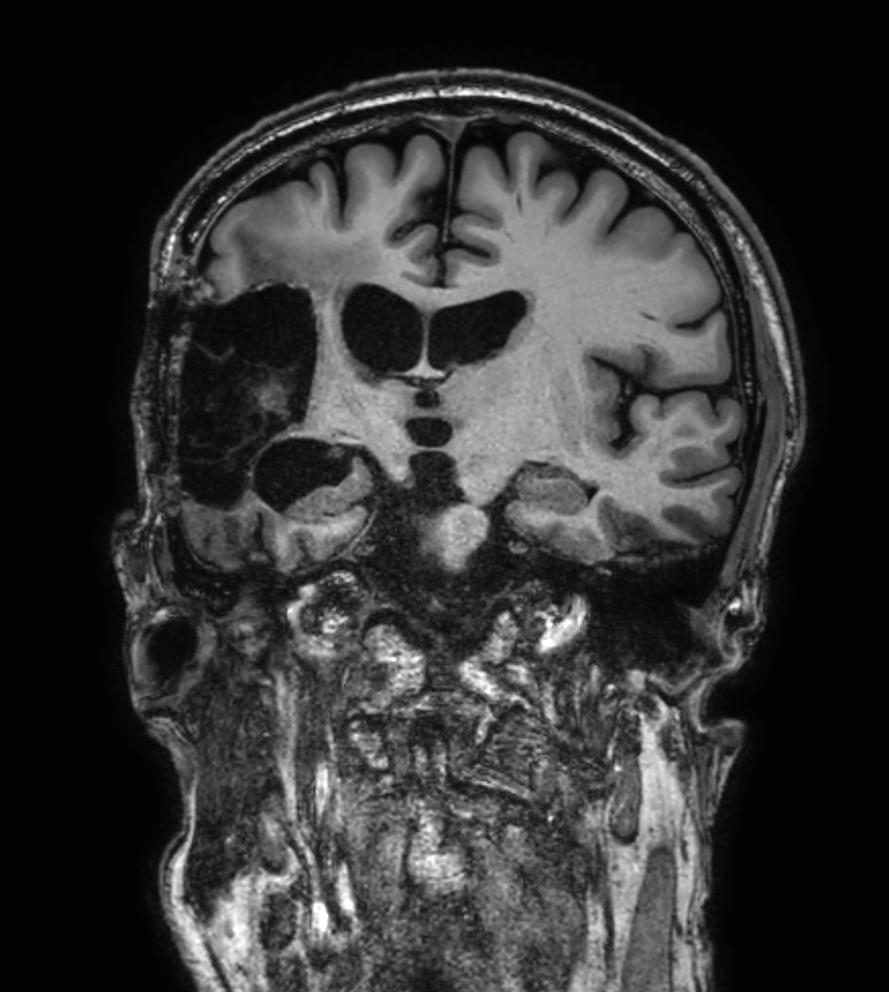

Brain glioblastoma, post-operative

Patient who was operated on glioblastoma

3D FLAIR - Axial reformat